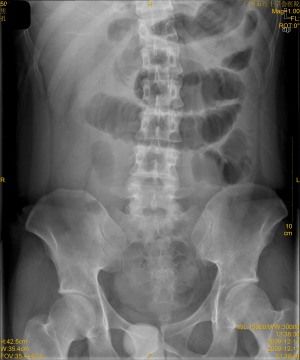

比较典型的腹部平片

腹部站立位平片讨论

腹部平片

立位腹部平片

腹部平片图

腹部气液平面x线图片

肠梗阻腹部平片图片

正常腹部立位平片图片

腹部平片气液平面

腹部立位片

腹部平片气液平面图片